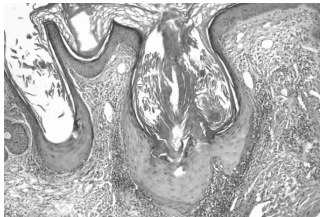

Аналогичную гистологическую картину мы получили и в нашем случае. Это терминальная стадия рубцовой алопеции без волосяных фолликулов, что позволяет поставить диагноз «псевдопеллада Брока» [13] (рис. 6–10).

Также при проведении патоморфологического исследования биопсийного материала было выявлено следующее: очаговый гиперкератоз, неравномерный гипергранулез, отек в шиповидном слое, вакуольная дистрофия клеток базального слоя, полосовидные или периваскулярные инфильтраты в верхних слоях дермы. Выявленные гистологические изменения более всего соответствуют красному плоскому лишаю, фолликулярной форме.

Рис. 6. Лимфогистиоцитарные инфильтраты вокруг волосяных фолликулов в их истмической зоне с их атрофией в виде «песочных часов» (слева). Рубцовая атрофия (справа) с полным исчезновением волосяных фолликулов и сальных желез. Мышцы, поднимающие волос, сохранены. Окраска гематоксилином и эозином, ув. ×40

Рис. 7. Тот же препарат, левая часть, ув. ×100

Рис. 8. Тот же препарат, правая часть, ув. ×100

Рис. 9. Лимфогистиоцитарные инфильтраты вокруг расширенных устьев волосяных фолликулов. Эпидермис между фолликулами не изменен. Окраска гематоксилином и эозином, ув. ×40

Рис. 10. Тот же препарат, ув. ×100, ув. ×400. Изменения эпителия устья волосяного фолликула: вакуолизация и скваматизация клеток базального слоя, гипергранулез, ортогиперкератоз, участки атрофии